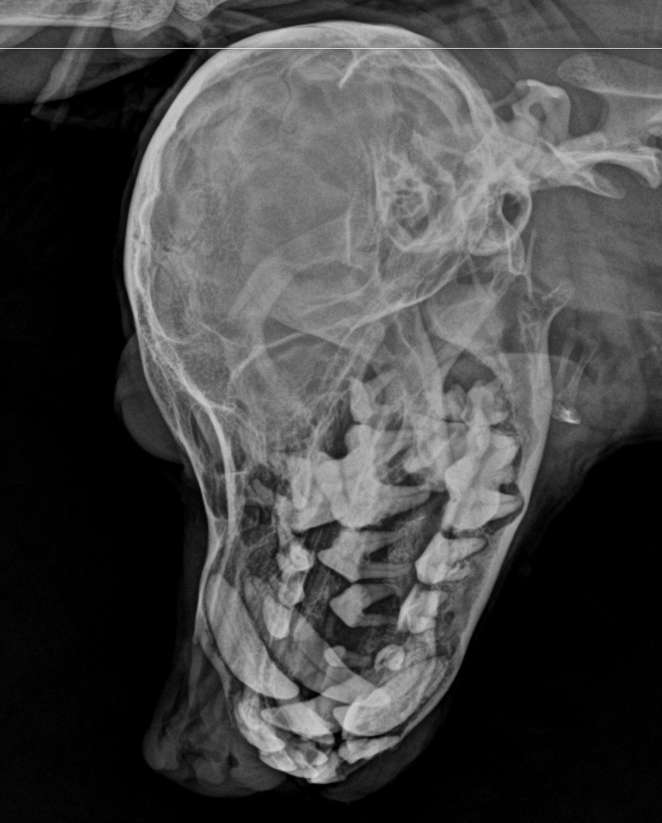

口腔检查时,医生发现了触目惊心的状况:满口牙齿覆盖着厚厚的黄褐色牙结石,牙龈红肿出血,部分牙齿已经松动。口腔X光片进一步显示,牙结石已侵蚀到牙龈深处,部分牙槽骨出现吸收迹象。这是典型的严重牙周病,如不及时处理,不仅会导致牙齿脱落,更可能引发全身性感染,危及宠物生命。